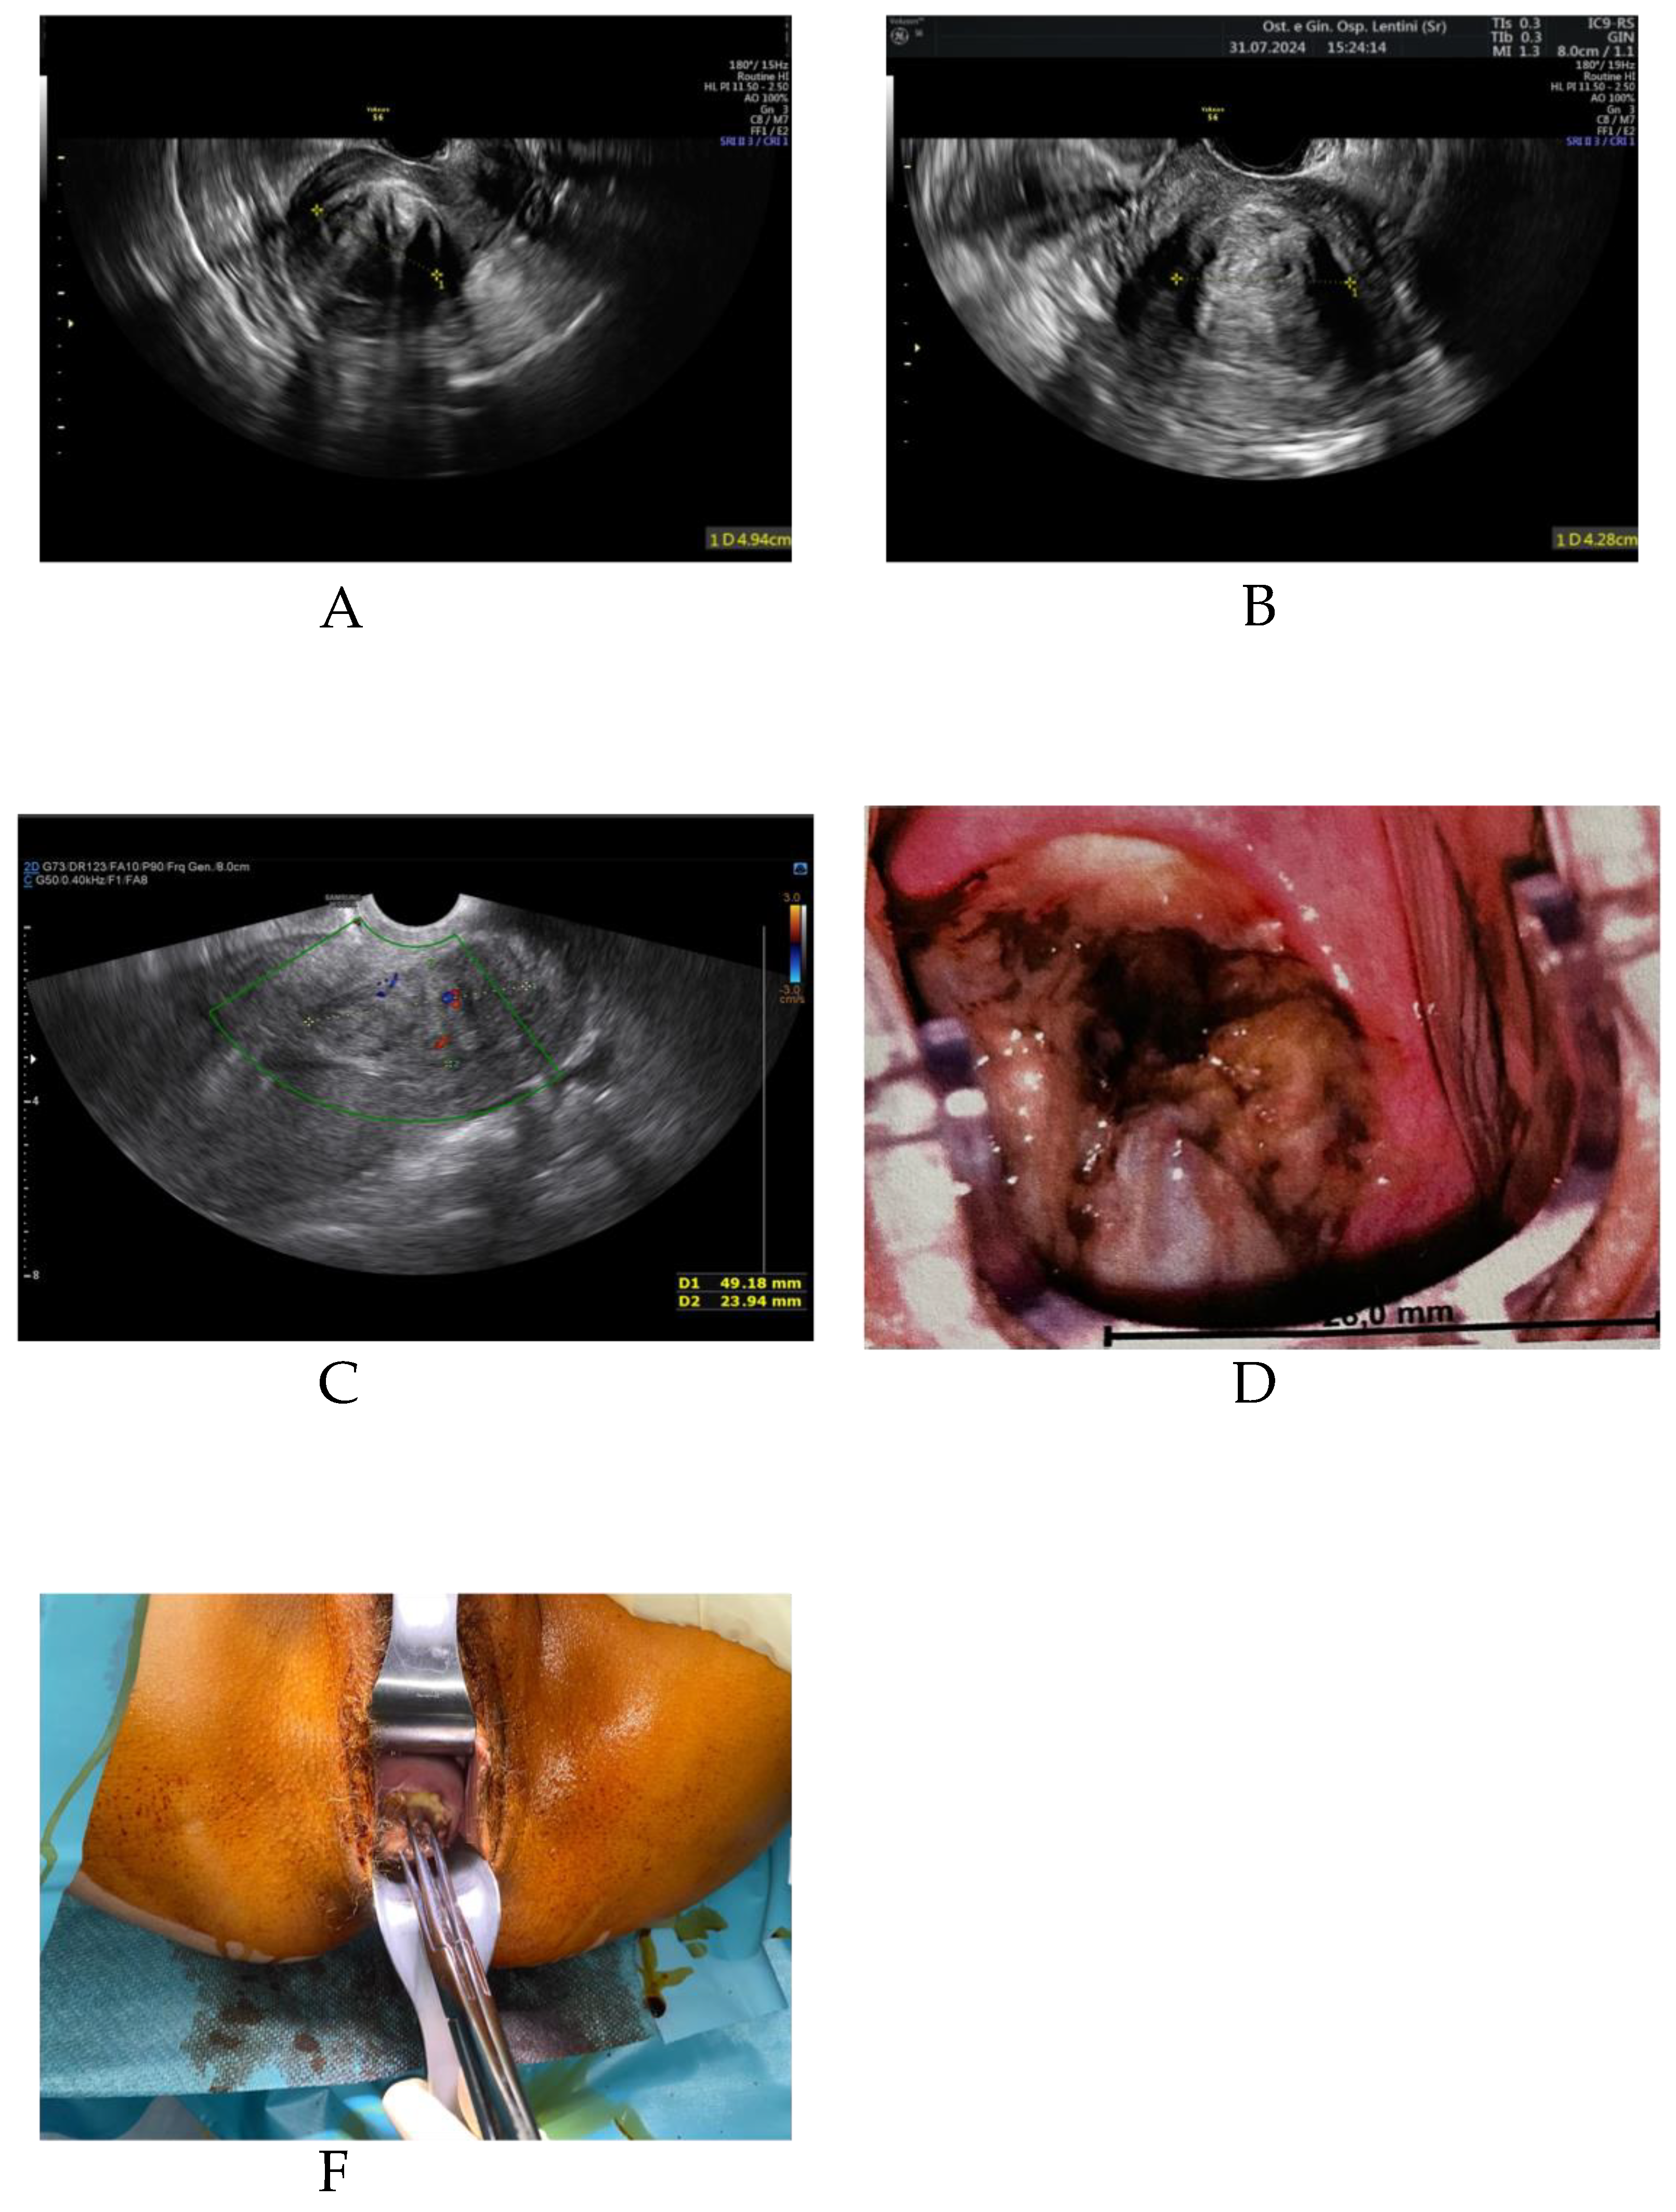

Uterine fibroids, also known as leiomyomas or myomas, are common gynaecological tumors that affect 20% to 40% of women aged 30 and over. In about one-third of cases, they cause symptoms such as heavy menstrual bleeding (hypermenorrhea), dysmenorrhea, dyspareunia, and pelvic pain. The choice of treatment depends on the number, size, and location of the fibroids, as well as the patient’s symptoms and reproductive goals. Historically, hysterectomy was the standard treatment for symptomatic fibroids, particularly for types 3, 5, 6, and 2–5 according to the FIGO classification. More recently, less invasive alternatives have become available. Transvaginal radiofrequency ablation (RFA) is a technique that allows fibroid treatment without surgical incision. The method uses an ultrasound-guided electrode inserted via the vaginal route into the fibroid tissue. The high-frequency alternating current produces localised heating (60–80 °C), leading to coagulative necrosis, cell death, ischemia, and loss of hormone receptor activity in the treated tissue. The patient, C.E., is a 41-year-old woman with a history of one spontaneous delivery and prior laparoscopic surgery for endometriosis. She presented to our gynaecology unit complaining of hypermenorrhea, pelvic pain, and fatigue due to anaemia. A transvaginal ultrasound identified a 5 cm uterine fibroid (FIGO type 2–5).In June 2024, she underwent transvaginal RFA. The procedure was completed without intraoperative or postoperative complications. One month later, the patient reported improvement in pelvic pain but continued to experience heavy menstrual bleeding. Follow-up ultrasound showed the fibroid had decreased by approximately 1 cm. Two months after the procedure, she returned with complaints of excessive hypermenorrhea, spotting, smelly vaginal discharge, and pelvic pain. Transvaginal ultrasound revealed the fibroid had migrated into the cervix with a vascular pedicle. Vaginal surgical removal was performed under general anesthesia. The procedure lasted 10 minutes and was completed without complications. The patient was discharged in good health. Histopathological analysis is pending. Uterine fibroids are benign tumors common in reproductive and perimenopausal women. They typically require treatment only when symptomatic, such as when causing heavy bleeding, anemia, or pain. Hysterectomy was historically the primary surgical option, but many minimally and non-invasive techniques are now available. Transvaginal RFA is a minimally invasive, incision-free method performed under ultrasound guidance. It allows for targeted fibroid ablation with minimal downtime and low complication rates. Fibroid expulsion is a rare post-RFA event. To date, only one similar case has been reported, from a hospital in Germany in 2023. Common symptoms of fibroid expulsion include vaginal bleeding, smelly discharge, and the sensation of a mass passing through the vagina. Fibroid removal via the vaginal route is safe and effective, even for large fibroids. In our case, we considered the expulsion beneficial, as the fibroid was completely removed without complications. However, this outcome could also represent a complication, especially if associated with infection, significant blood loss, or surgical risks. The estimated risk of fibroid expulsion after RFA is approximately 1%–1.5%. In cases where expulsion occurs, timely vaginal removal can lead to a favorable outcome. It remains unclear whether this rare event should be classified as a complication or a potential therapeutic benefit. (A) Transvaginal ultrasound showing a 5 cm FIGO type 2–5 fibroid prior to RFA. (B) One month post-RFA, showing a reduction in fibroid size. (C) Two months post-RFA, Doppler ultrasound revealing fibroid descent into the cervical canal.(D) Cervical fibroid visualized during colposcopic examination (E) Intraoperative image showing the removal of the expelled fibroid.